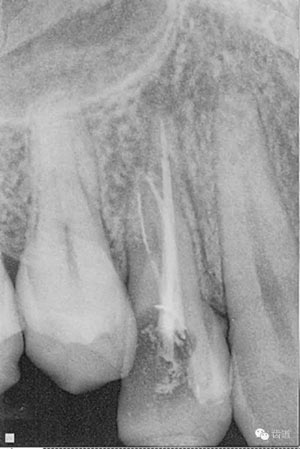

檢查顯示:近頰及腭根充填恰填,遠(yuǎn)頰根管內(nèi)有少許充填物影像。根尖明顯低密度影像。

處理:顯微根管治療。放置橡皮障,去除暫封,顯微鏡下超聲去除頰側(cè)根管上段部分牙本質(zhì),探及遠(yuǎn)中根管口,見有糊劑遮蓋。Path file根管疏通,M Two根管預(yù)備至2506#,配合3%次氯酸鈉和17%EDTA超聲蕩洗,干燥根管,放置氫氧化鈣糊劑,zoe暫封。

處理:放置橡皮障,去除暫封,超聲結(jié)合2%CHX清除遠(yuǎn)頰根管內(nèi)氫氧化鈣糊劑,主牙膠試合后95%酒精沖洗干燥根管,結(jié)合AH Plus糊劑連續(xù)波熱牙膠垂直加壓充填根管,樹脂分層粘接修復(fù)牙體。建議定時(shí)復(fù)診進(jìn)行嵌體修復(fù),患者未執(zhí)行。